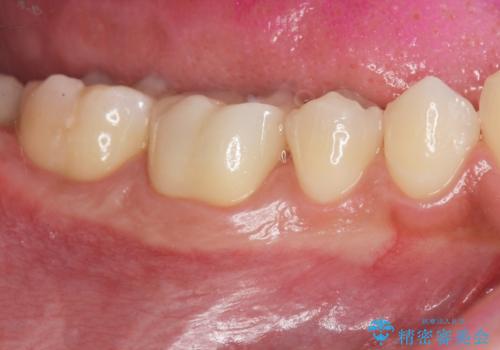

2.

2. 放置してしまった虫歯の治療の治療中